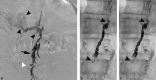

Traumatic chylothorax occurs more often now than in historic reports. In part, this is due to the increased ability to perform more advanced and aggressive thoracic resections and cardiovascular surgeries as well as the improved mortality of cancer patients. If untreated, chylothorax can result in significant morbidity and mortality, particularly in patients with underlying malignancy. Thoracic duct embolization for chylothorax was the first successful lymphatic intervention and has been performed for over 20 years. An overview of the clinical and technical approach to thoracic duct embolization for traumatic chylothorax is presented in addition to a review of outcomes.